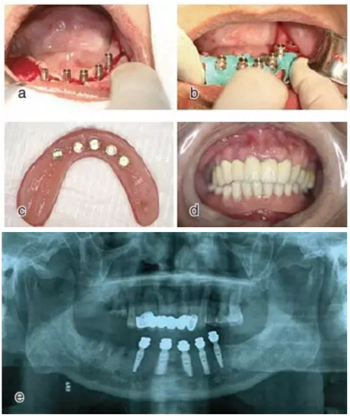

種植后修復(fù)

戴上套筒冠基臺進(jìn)行即刻修復(fù)。注意不是所有植入的種植體都可以進(jìn)行即刻修復(fù),醫(yī)師可以通過扭力值并結(jié)合ISQ松動度測量值來選擇修復(fù)的種植體。

圖18 進(jìn)行即刻修復(fù):a.戴上基臺;b.在基臺上戴入套筒冠;c. 套筒冠固位到原有義齒上;d.患者戴上有套筒冠的覆蓋義齒;e. 即刻修復(fù)完成后曲面體層片